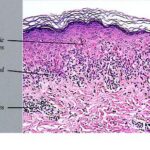

Histopathology. EM is considered the prototype of the vacuolar form of interface dermatitis . The early changes include vacuolization of the basal cell layer; tagging of lymphocytes along the dermal-epidermal junction; and a sparse, superficial, perivascular lymphoid infiltrate . Necrosis of individual keratinocytes in the basal unit occurs, which is the hallmark of EM. Because of its acute nature, there is an orthokeratotic stratum corneum. Mild spongiosis, papillary dermal edema, and extravasation of red blood cells are seen. As the lesion becomes more developed, there is a moderate lichenoid infiltrate of Iymphohistiocytes at the dermal-epidermal junction with exocytosis. More apoptotic keratinocytes within and above the basal epidermal layer are present. The |

intensity of epidermal necrosis varies from vacuolated individual keratinocytes surrounded by lymphocytes (satellite cell necrosis) at the basal unit to confluent necrosis in association with intraepidermal and subepidermal vesicles. The dermal infiltrate comprises lymphocytes and histiocytes. Eosinophils may also be present. Although one study has noted a significant number of eosinophils in drug-induced EM, this has not been noted by others. In the authors’ estimation, a generous number of eosinophils exclude EM. One study has found that an acrosyringium concentration of apoptotic keratinocytes in EM is a clue to a drug etiology . In early lesions of SJSITEN, apoptotic keratinocytes are observed scattered in the basal layer of the epidermis. In established lesions, there are numerous necrotic keratinocytes, even full-thickness epidermal necrosis, and a subepidermal bulla. The dermal inflammatory infiltrate is sparser in TEN than in EM (Fig. 9-278). Extravasated erythrocytes are commonly found within the blister cavity. Melanophages within the papillary dermis occur in late lesions. Eccrine epithelium shows a variety of changes from basal cell apoptosis to necrosis of the duct. |

In general, EM shows less epidermal necrosis, more dermal inflammation, and exocytosis, whereas SJS and TEN reveal more epidermal necrosis, less dermal inflammation, and exocytosis. However, due to the overlapping histologic features among EM, SJS, and TEN, histologic examination-while important for recognizing the spectrum of disorders-is not reliable for classifying the disease. Correlation with clinical presentation is essential. |